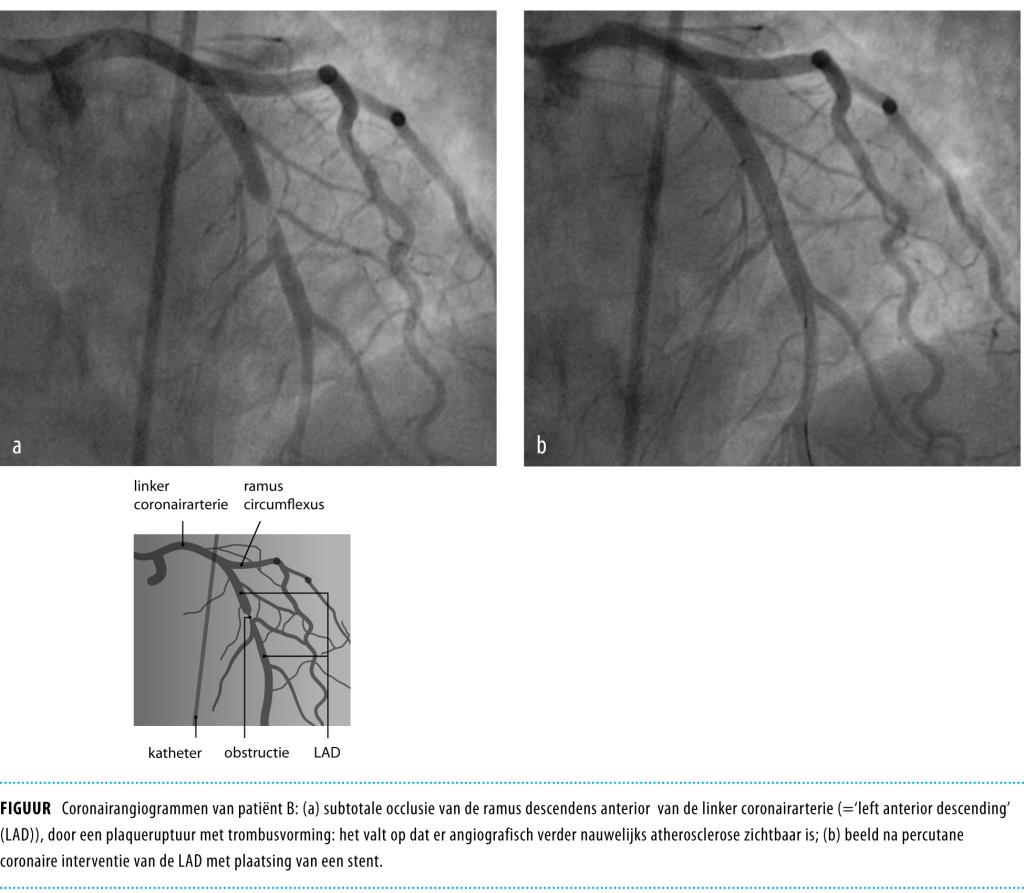

Met als waarschijnlijkheidsdiagnose ‘pijn op de borst door psychische stress’ krijgt zij pijnstilling voorgeschreven met paracetamol. Nadat zij is vertrokken uit de HAP zakt zij 50 m verder bewusteloos in elkaar. Er wordt gestart met reanimatie en bij aankomst van de ambulance wordt ventrikelfibrilleren vastgesteld, waarvoor zij met succes wordt gedefibrilleerd. Daarna herstelt de circulatie en wordt patiënte weer aanspreekbaar. Op het ecg in de ambulance is er een forse ST-T-elevatie in de afleidingen V2-V6 en aVL, passend bij een acuut voorwandinfarct. Bij het spoed-CAG heeft zij een subtotale occlusie van de ramus interventricularis anterior van de linker coronairarterie (‘left anterior descending’ (LAD)) met veel trombusmateriaal en een licht verminderde bloedstroom naar perifeer. Na aspiratie van de trombus wordt er een directe stent-implantatie verricht (figuur). Het verdere klinische beloop is ongecompliceerd en op het echocardiogram nadien is geen duidelijk infarctlitteken te zien.

Figuur 1